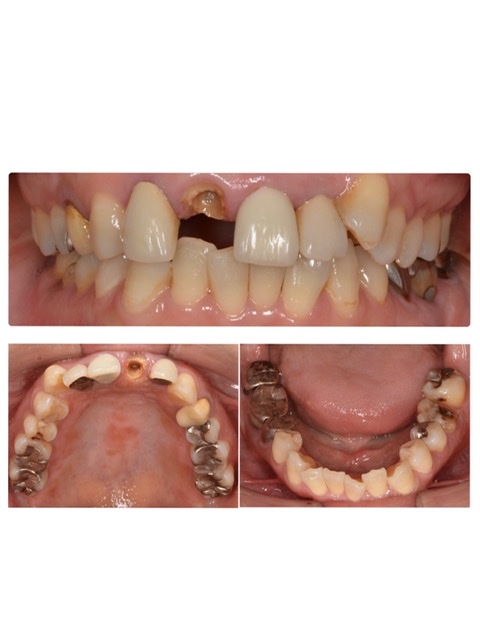

全顎治療

インプラント治療とセラミック治療の併用で、全体的に審美性を改善するための治療が行われました。歯の形、並び、色ともに不自然さがなく、見た目が美しく改善されています。

| リスク・副作用 | 治療終了後のメンテナンス不足による歯周病、歯ぎしりや過剰な噛み締めによるセラミックの破損 |

|---|---|

| 費用 | インプラント治療1本55万円(税込)、セラミック治療1本22万円(税込) |

| 期間 | 約7カ月 |